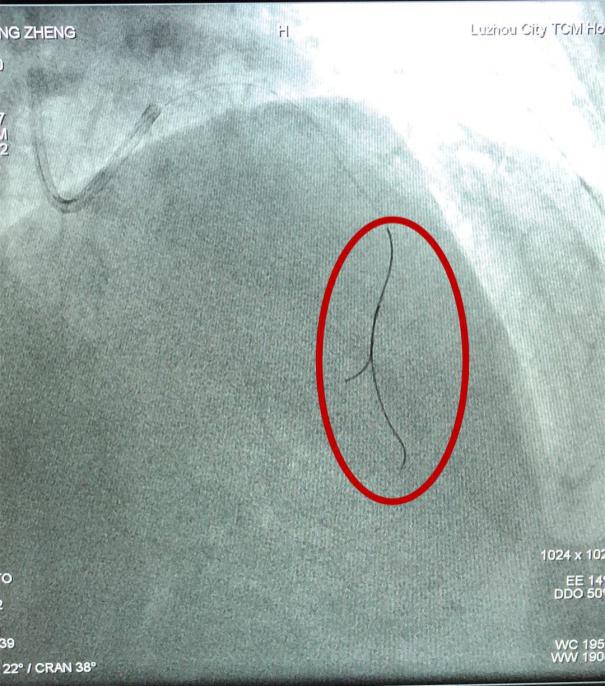

压力导丝(如图中红圈内所示)

在冠脉内测量FFR(血流储备分数)